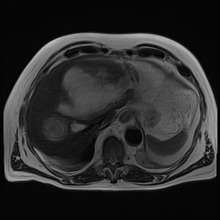

Amoebic liver abscess

A amoebic liver abscess is a type of liver abscess caused by amebiasis.[1] It is the involvement of liver tissue by trophozoites of the organism Entamoeba histolytica and of is abscess due to necrosis.